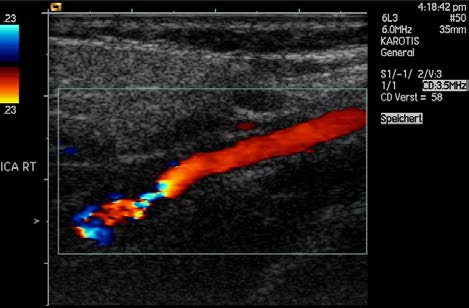

Another major use of ultrasound in medical diagnostics is to detect motion and determine velocity through the Doppler shift of an echo, known as

Doppler-shifted ultrasound. This technique is used to monitor fetal heartbeat, measure blood velocity, and detect occlusions in blood vessels, for

example. (See Figure 17.47.) The magnitude of the Doppler shift in an echo is directly proportional to the velocity of whatever reflects the sound.

Figure 17.47 This Doppler-shifted ultrasonic image of a partially occluded artery uses color to indicate velocity. The highest velocities are in red, while the lowest are blue. The blood must move faster through the constriction to carry the same flow. (credit: Arning C, Grzyska U, Wikimedia Commons)